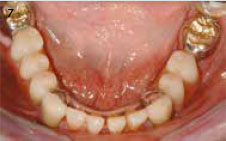

Afb. 7

In de onderkaak zijn kronen gemaakt op de 33 en 43 met mini-SGschuifslotjes en volledige kronen op 36 en 47 waarop een frame afsteunt.